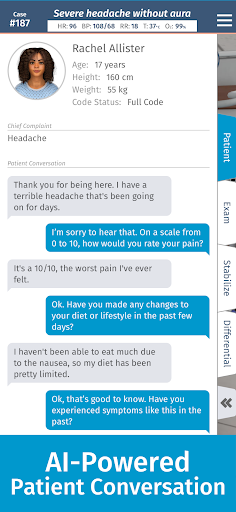

• AI của bệnh nhân cho phép thực hành với việc ghi lại bệnh sử

— Bệnh nhân AI —

Chúng tôi rất vui mừng được giới thiệu Bệnh nhân AI — tính năng hội thoại bệnh nhân mới của chúng tôi tận dụng những tiến bộ mới nhất trong trí tuệ nhân tạo. Các cuộc hội thoại AI của bệnh nhân là không giới hạn đối với người đăng ký Pro và khả dụng trên cơ sở hạn chế đối với người dùng Cơ bản và người dùng miễn phí.